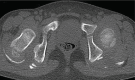

Myossitis ossificans (MO) is a benign disorder characterized by heterotopic bone formation in skeletal muscle. It is divided in three types, fibrodysplasia ossificans progressive (FOP), myositis ossificans circumscripta or traumatica (MOT) and myositis ossificans without a history of trauma (non traumatic or pseudomalignant MO). Myositis ossificans is extremely rare in children younger than 10 years. We present the clinical and radiological findings of two 5-year-old children with pseudomalignant MO due to prolonged immobilization. Plain x-ray films and CT scan with their characteristic findings of mature bone in the periphery of the lesion with smooth contour and well separated from the bone, enabled us to diagnose the lesion. To the best of our knowledge, no such cases have been reported in the literature.